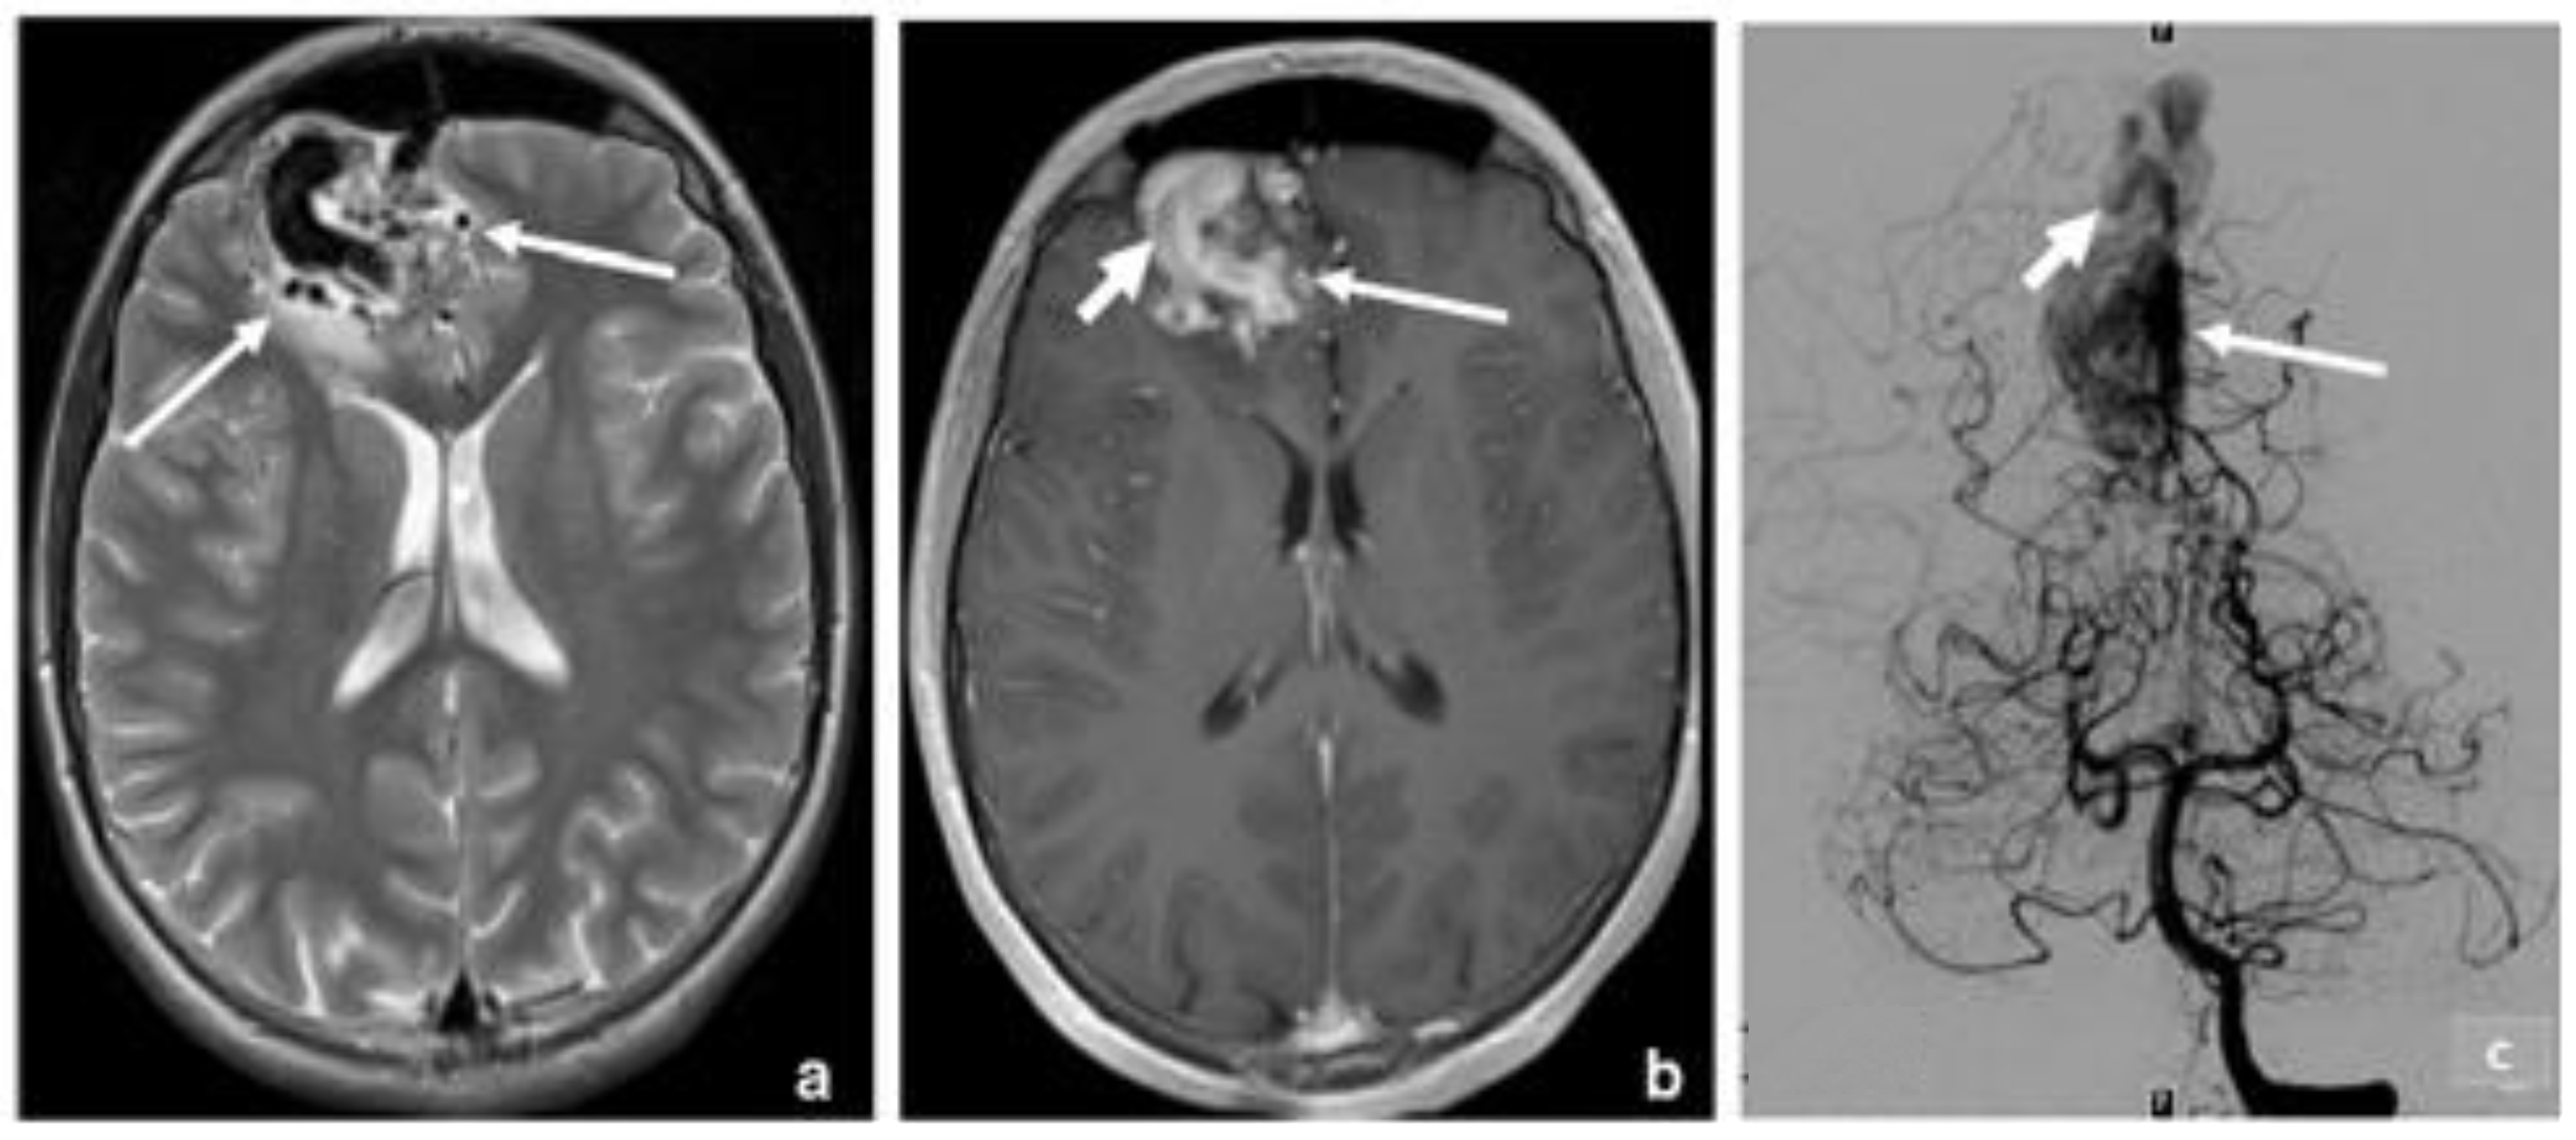

3.2. Arteriovenous Malformation (AV Angioma, Cirsoid Angioma)

- Healy, V.; O’Halloran, P.J.; Husien, M.B.; Bolger, C.; Farrell, M. Intermixed Arteriovenous Malformation and Hemangioblastoma: Case Report and Literature Review. CNS Oncol. 2020, 9, CNS66. [Google Scholar] [CrossRef] [PubMed]

- Gross, B.A.; Du, R. Diagnosis and Treatment of Vascular Malformations of the Brain. Curr. Treat. Options Neurol. 2014, 16, 279. [Google Scholar] [CrossRef]

- Settecase, F.; Hetts, S.W.; Nicholson, A.D.; Amans, M.R.; Cooke, D.L.; Dowd, C.F.; Higashida, R.T.; Halbach, V.V. Superselective Intra-Arterial Ethanol Sclerotherapy of Feeding Artery and Nidal Aneurysms in Ruptured Cerebral Arteriovenous Malformations. AJNR Am. J. Neuroradiol. 2016, 37, 692–697. [Google Scholar] [CrossRef] [PubMed] [Green Version]

- Chen, C.-J.; Norat, P.; Ding, D.; Mendes, G.A.C.; Tvrdik, P.; Park, M.S.; Kalani, M.Y. Transvenous Embolization of Brain Arteriovenous Malformations: A Review of Techniques, Indications, and Outcomes. Neurosurgical. Focus 2018, 45, E13. [Google Scholar] [CrossRef] [PubMed] [Green Version]